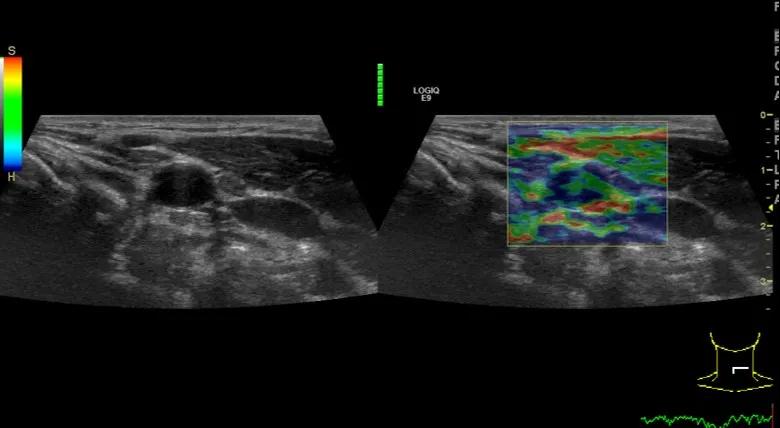

随后,徐栋教授进一步分享了五个临床实战病例,带来了更直观的热消融治疗经验。第一个病例是62岁肺癌患者,术后1年余发现双侧锁骨上淋巴结复发,侵犯神经,存在静脉回流、淋巴回流障碍,肿胀、疼痛非常明显。影像显示患者淋巴结边界不清、形态不规则,存在浸润,血流强化增强。由于患者在系统治疗后进展,且主要目的缓解症状、减瘤。局麻下行热消融术,从后向前逐层消融,热消融之后超声造影即刻评估显示完全充盈缺损,完全覆盖病灶。

(病例1图例)